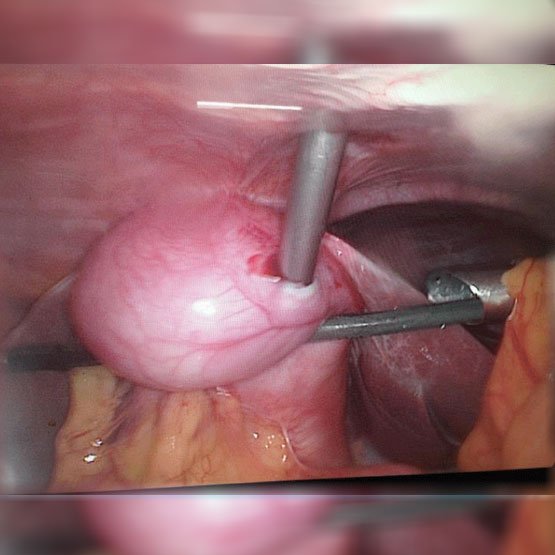

ByRL GYNAECOLOGY INSTRUMENTS

ByRL Uterine Manipulator

The fully visualization of the uterus and the adnexa is the important basis for a good gynecological laparoscopic surgery. An Uterine Manipulator that can be adjusted to different angles allows the operator to flex and rotate the uterus so that it can be brought into an optimal position.

Uterine Manipulator are available in 2 types :

- Uterine Manipulator “Marwah” type

- Uterine Manipulator “Sukhadia” type

Product Features :

- Made up of Medical Grade plastic / polycarbonate and Stainless steel.

- Fully reusable